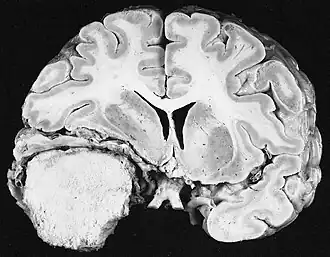

Hersentumoren zijn neoplasmata die zich in de hersenen ontwikkelen. Tumoren zoals meningeoom, die vanwege hun massa samendrukken maar niet doordringen in de hersenen, en hypofyse- en epifysaire tumoren, die zich op de hersenstam bevinden, worden vaak ten onrechte hersentumoren genoemd. De term intracraniële tumoren vat deze nauwkeuriger samen.

Primaire CZS-tumoren omvatten een verscheidenheid aan pathologische entiteiten, elk met zijn eigen natuurlijke geschiedenis. Vanwege het feit dat gliale tumoren (gliomen) alleen al verantwoordelijk zijn voor bijna 40 procent van deze tumoren, kan eerst onderscheid worden gemaakt tussen gliomen en niet-gliale tumoren. De meest voorkomende gliomen zijn astrocytomen (afkomstig van gliale astrocytcellen), oligodendrogliomen (afkomstig van oligodendrogliale cellen) en ependymomen (afkomstig van ependymcellen).

Kwaadaardige primaire tumoren van het centrale zenuwstelsel zijn relatief zeldzaam en zijn goed voor ongeveer 2% van alle kwaadaardige neoplasmata. Tumorziekten van het centrale zenuwstelsel komen in 95% voor in de hersenen zelf en 5% in hersenvliezen, hersenzenuwen en ruggenmerg. Ze kunnen op elke leeftijd voorkomen en het risico op het ontwikkelen van de ziekte neemt toe met de leeftijd. Bij volwassenen kunnen gliomen histologisch afkomstig zijn van het steunweefsel van de zenuwcellen, waarvan ongeveer 75% van de glioblastomen astrocytomen graad IV met een ongunstige prognose. Embryonale tumoren overheersen bij zuigelingen en jonge kinderen. In Duitsland kregen in 2016 ongeveer 3.970 mannen en 3.460 vrouwen een kwaadaardige tumor van het centrale zenuwstelsel. Gemiddeld zijn de overlevingspercentages 21% voor mannen en 24% voor vrouwen. Statistieken omvatten zelden goedaardige CZS-tumoren, die voorkomen bij ongeveer 6.000 nieuwe gevallen per jaar. Ongeveer 65% daarvan komt van de hersenvliezen. Vrouwen worden veel vaker getroffen. Als ze niet worden behandeld met chirurgie of bestralingstherapie, kunnen zelfs goedaardige tumoren fataal zijn door compressie als gevolg van progressieve groei in de gesloten schedelruimte. De meest voorkomende kwaadaardige intracraniële CZS-tumor is glioblastoom, de meest voorkomende goedaardige is meningeoom.

Glioblastoom

De meest voorkomende en kwaadaardige gliaceltumoren zijn glioblastomen. Ze bestaan voornamelijk bij volwassenen uit een heterogene massa van slecht gedifferentieerde astrocytoomcellen. Ze komen meestal voor in de hersenhelften, meer zelden in de hersenstam of het ruggenmerg. Behalve in zeer zeldzame gevallen, zoals alle hersentumoren, reiken ze niet verder dan de structuren van het centrale zenuwstelsel.